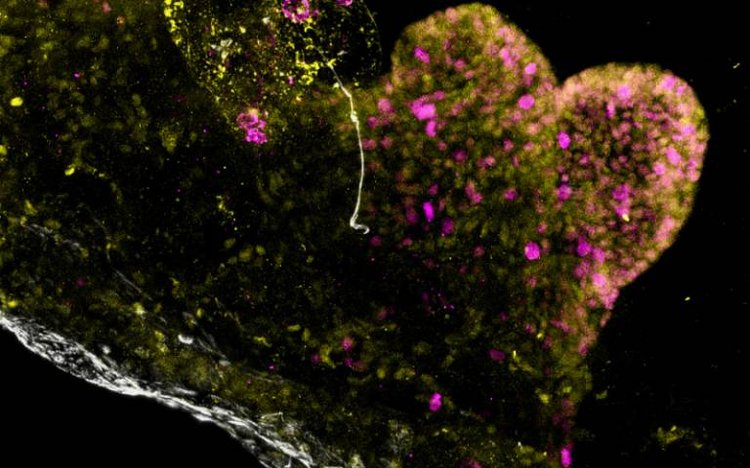

Mini stomach organoid

Published in Nature Biomedical Engineering, the researchers explain how they isolated stem cells from stomach samples from patients and grew them under special laboratory conditions in a petri dish to create mini-stomachs, known as organoids, that mimic the behaviour of a human stomach.

They grew separate organoids for each of the three main stomach regions and then combined – or “assembled” – them into a single version, known as an assembloid version. This is the first time this has been successfully achieved.

The research team found that not only did each organoid keep the characteristics of the area of the stomach from which it was grown, but they communicated with each other in the same way that the full-sized human organ does. The assembloids were also able to produce stomach acid, which is a key function of the stomach and helps the body digest food.